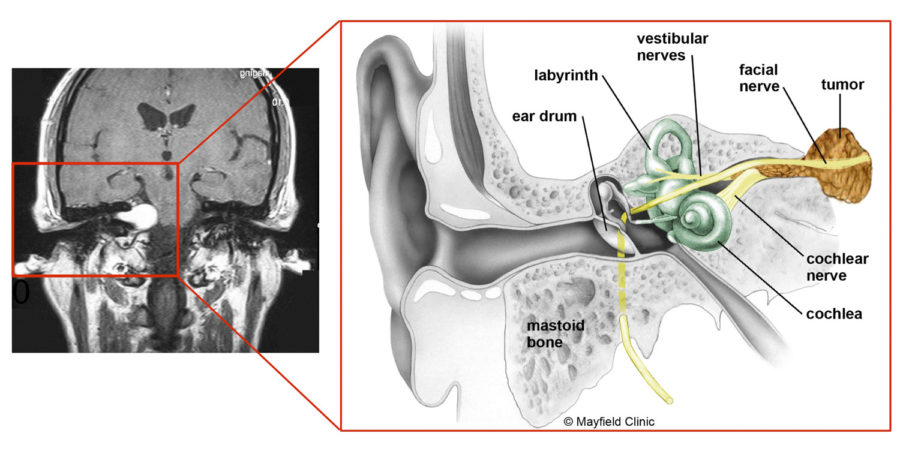

This image shows a benign tumor of the vestibulocochlear nerve (VIII cranial nerve). Image courtesy of Mayfield Clinic

As branches of the vestibulocochlear nerve that lead from the inner ear to the brain directly influence balance and hearing, pressure from an AN can cause hearing loss, ringing in the ear and unsteadiness.